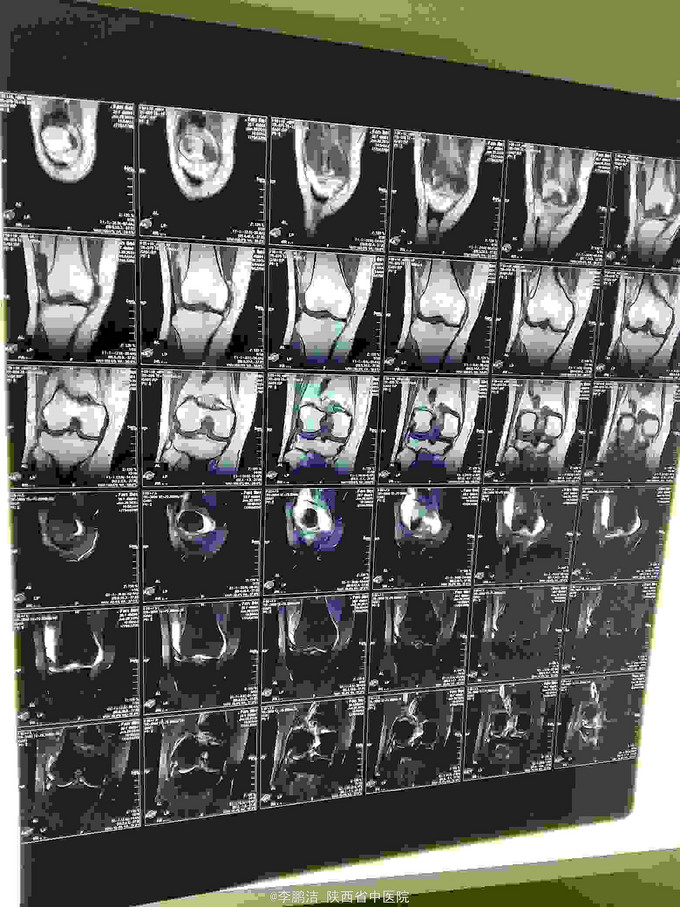

主诉:双膝关节疼痛,间断发作4年余。 现病史:患者于入院4年前因劳累后出现双膝关节疼痛,久行及上下楼梯时疼痛加剧,经休息疼痛好转,故当时未能引起重视,未进行系统治疗。其后因疼痛在当地诊所行局部理疗(具体治疗不详),经治疗后疼痛当时好转。之后,双膝关节疼痛症状时轻时重,间断性发作。近来,双膝关节疼痛症状加重,患者为求进一步治疗,遂于今日来我院就诊,门诊以“膝骨关节病”之诊断收住我科。

查体:脊柱生理弯曲尚可,L3-S1棘突及椎旁无压痛,双膝关节无肿胀,局部皮肤温度不高,内外侧副韧带止点压痛(+),髌韧带止点处压痛(-),鹅足滑囊处压痛(+),浮髌试验(-),髌骨摩擦试验(+),抽屉试验(-),双膝关节活动度明显受限;生理反射存在,病理反射未引出。

中医诊断:骨痹症 气滞血瘀 西医诊断:1、膝骨关节病 2、2型糖尿病 3、高血压 中医治疗方案:中药封包治疗、穴位贴敷舒筋通络。 西医治疗方案:口服阿托伐他汀钙片降脂,盐酸二甲双胍片、阿卡波糖片降糖,苯磺酸左旋氨氯地平片降压,硫酸氨基葡萄糖胶囊保护软骨面;患者夜间出现胸闷、气短,可行动态心电图、活动平板试验排除心脏疾病。 可给予口服活血化瘀,行气宽中之中药汤剂,具体方剂如下: 生地黄25g 当归10g 川芎15g 桃仁10g 红花10g 赤芍15g 柴胡10g 枳壳10g 怀牛膝15g 桔梗10g 生甘草6g 黄连10g 半夏(清半夏)15g 瓜萎15g 山栀10 7付水煎服 一日一剂